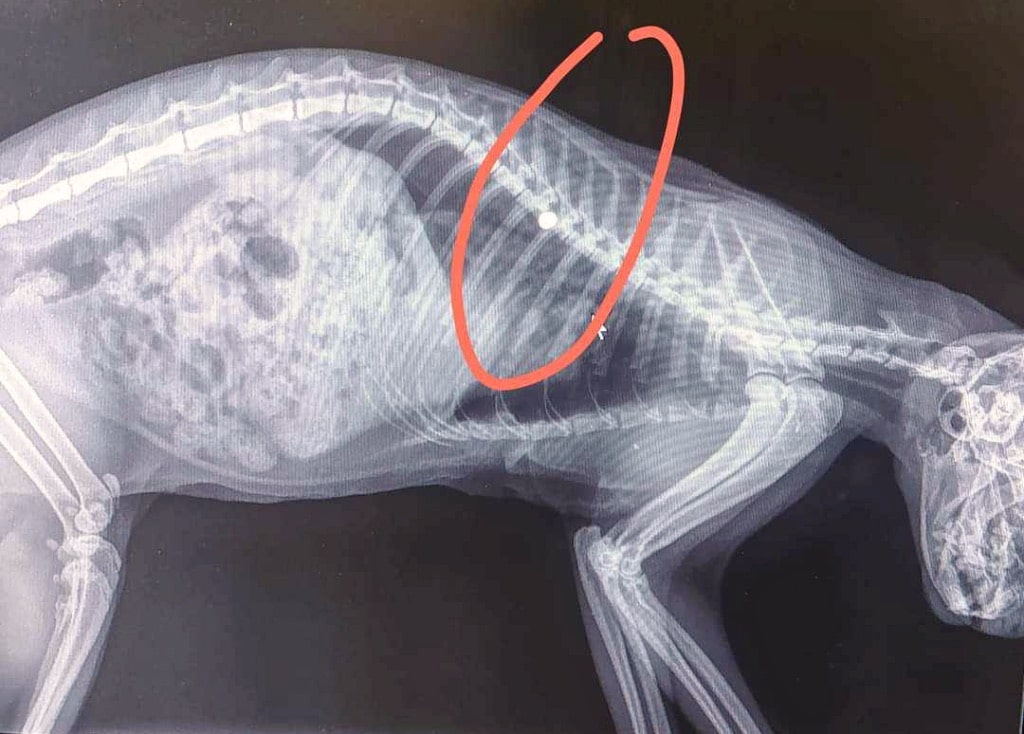

Ένα θλιβερό περιστατικό με δολοφονία ζώου σημειώθηκε στον Άγιο Γεώργιο! Άτυχο ζώο βρέθηκε δολοφονημένο στην...